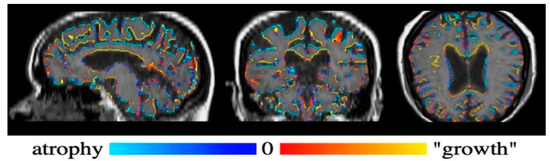

Figure 4 shows the Siena output color-coded image of the brain, while Figure 5 shows the brain parenchymal fraction in the axial image from August (Figure 5A) and September (Figure 5B), before and after DFPP procedure, respectively, with a TIV reduced by 2.14% in the latter, where subarachnoid spaces appeared to increase as expected.

Figure 5.

Pre-to-post registration axial images of the brain, before (A) and after (B) the DFPP procedure respectively, identified using the Siena tool of the FSL software. Yellow color indicates the brain parenchymal fraction, red color the ventricular system and subarachnoid spaces. Given the 2.14% reduction of total intracranial volume (TIV), note the expected prevalence of the red color in B indicating the involvement of subarachnoid spaces, with TIV = 1300.4 mL with respect to A with TIV = 1328.8 mL.

This reduction in the brain tissue volume resulted mainly from the shrinkage in grey matter and peripheral grey matter, measuring 511.2 mL and 402.9 mL respectively, according a % reduction of 1.16 and 1.14, respectively. The total cerebrospinal fluid (CSF) volume underwent a % net increase of 1.22, despite the ventricular space reduction by 1.11%. Finally, the white matter volume increased 1.14%. The patient underwent an intensive rehabilitation program with exercises focused on gait-reeducation and proprioceptive facilitation.